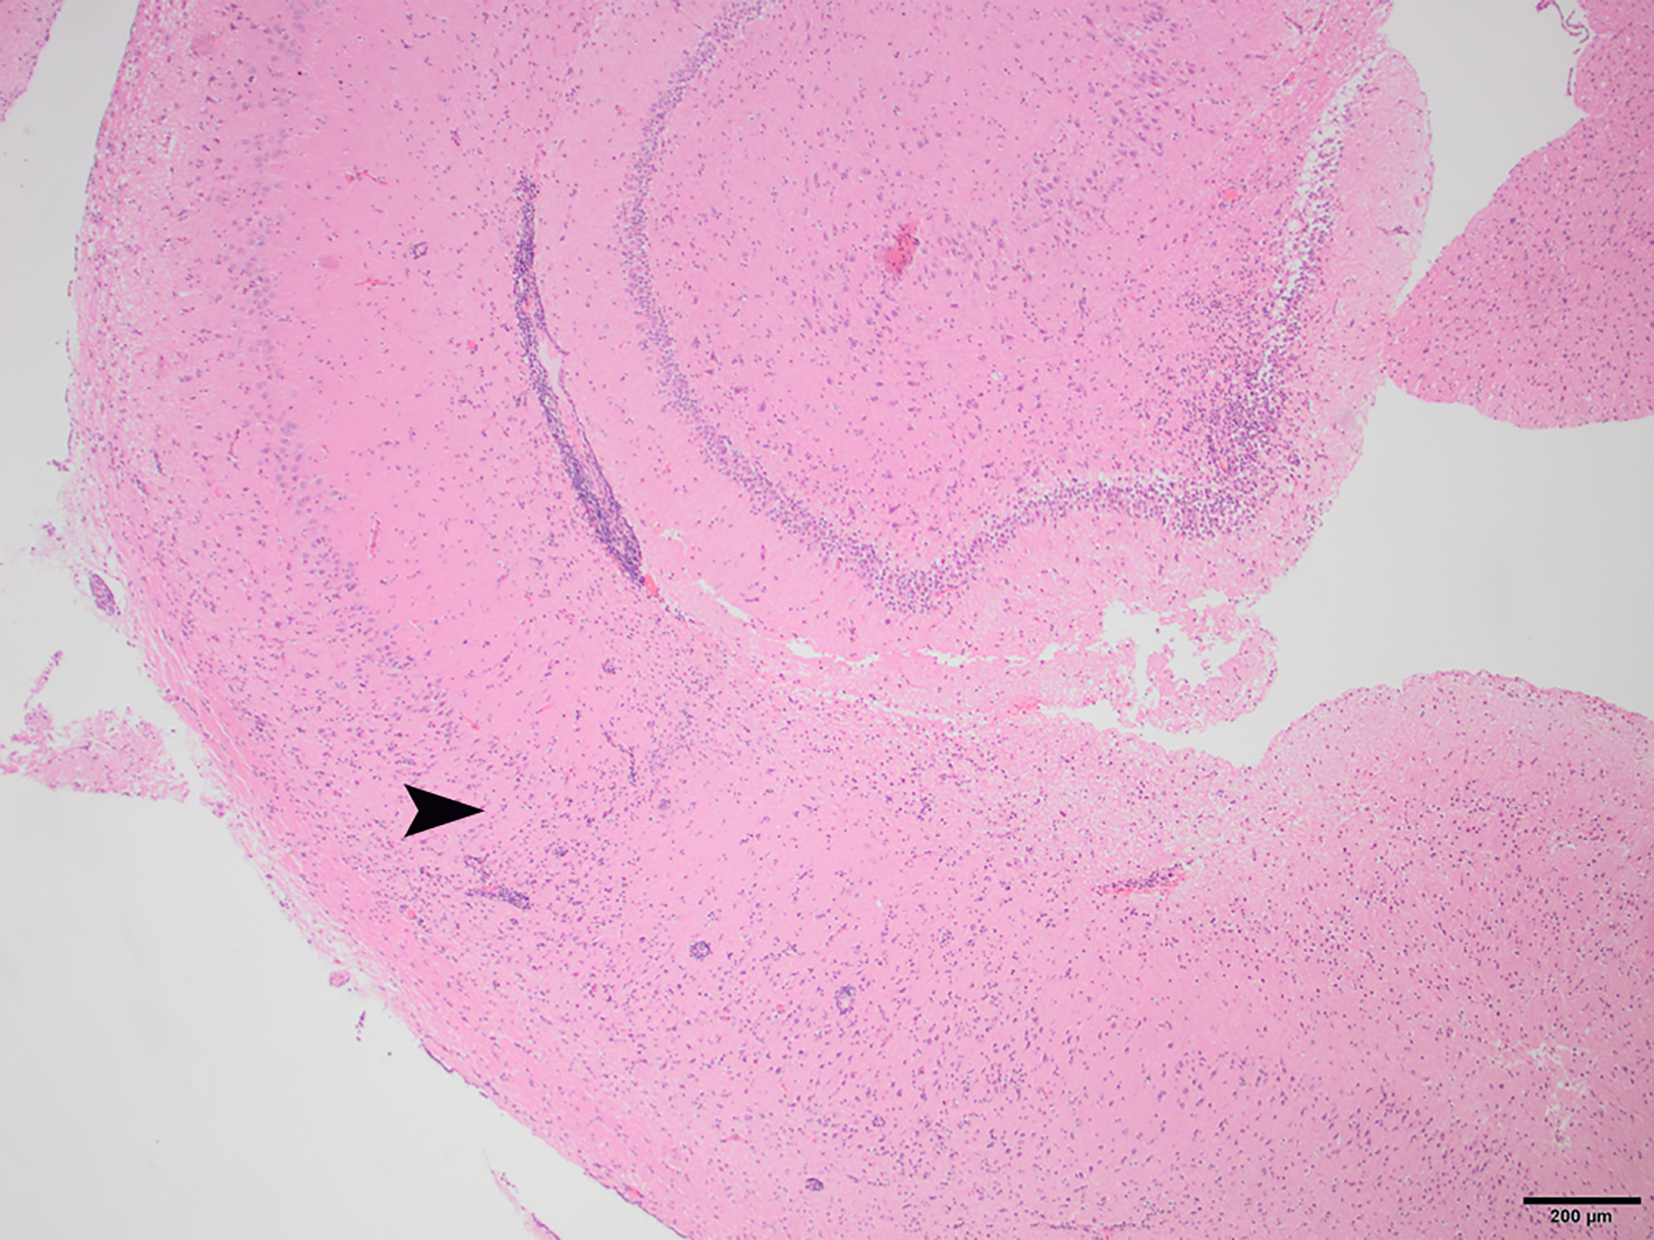

To determine whether DFS was associated with neurological inflammation, gross necropsy was performed on a total of 83 foxes. For 15 foxes (six captive neurologically affected foxes and nine pseudo-control foxes), paired histology and infection status data were available for a range of neurotropic agents, excluding three captive foxes for which there were no formalin fixed samples (excluded from further analysis). Histological evidence of non-suppurative inflammation was detected in 5 samples: N2, N4, N6, and N8 showed lesions consistent with meningoencephalitis largely centered on the grey matter (polioencephalitis) (Figures 1–4), while C1 showed meningitis alone without concurrent involvement of the neuropil (Figure 5). All five affected tissues displayed prominent perivascular cuffing of inflammatory cells, with varying degrees of infiltration of the neuropil. Inflammatory infiltrates ranged from mainly lymphocytic (N2, Figure 1) to mixed lymphoplasmacytic (N4, Figures 2, 3; N8, Figure 4). Changes included mild gliosis, mild satellitosis, and neuronal changes, including hypereosinophilia, shrinkage, and angular cell bodies indicative of degeneration. N4 in particular showed marked effacement of the normal hippocampal architecture (Figure 2). On histological examination of sections from N8 (Figure 4), the presence of an intravascular larva was noted, prompting the addition of the A. vasorum PCR assay.

Figure 1

N2, H&E stain, 100×: Inflammation of the superficial grey matter with primarily lymphocytic infiltrates (non-suppurative polioencephalitis; arrowhead) with meningitis (arrow). Moderate gliosis and satellitosis are also present. At higher magnifications, shrunken, angular, hyper-eosinophilic neuronal cell bodies are observed, consistent with neuronal degeneration and early necrosis.